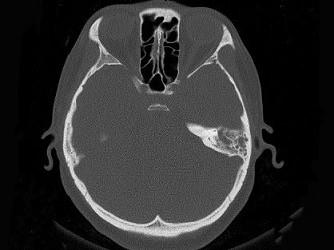

问题 女,34岁,左耳鸣,听力下降两个月,PE:左外耳道有脓性分泌物,鼓膜充血水肿,左中耳腔内软组织影,CT检查如图,最可能诊断为 ( )

选项 A、肉芽肿形成 B、中耳结核 C、中耳癌 D、胆脂瘤 E、乳突癌

答案 A